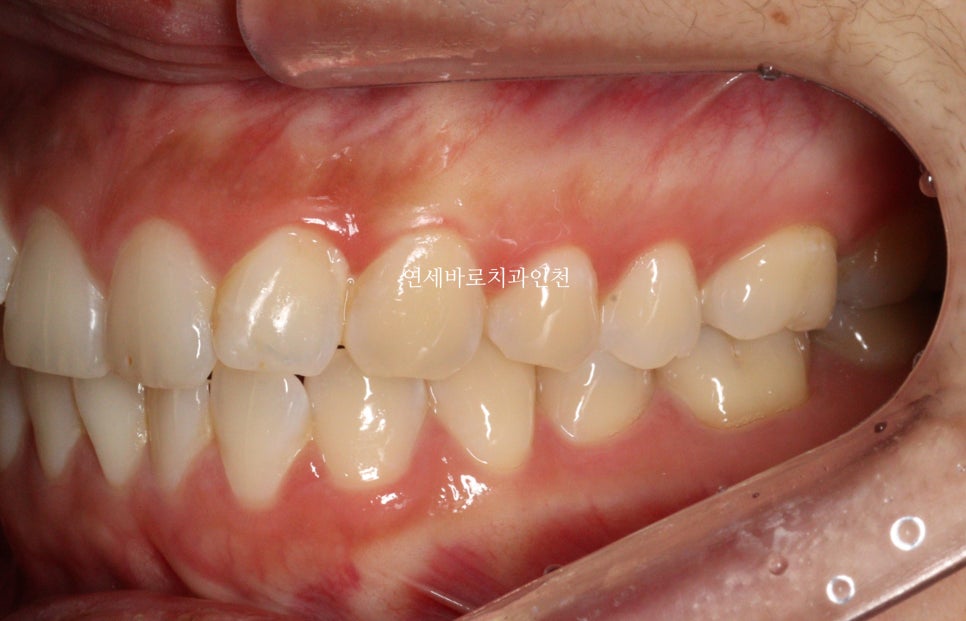

전후 측면 모습입니다.

치아가 확실히 후방이동을 하며 배열되었습니다.

조금 더 자연스러운 입술의 위치를 확인할 수 있었습니다.